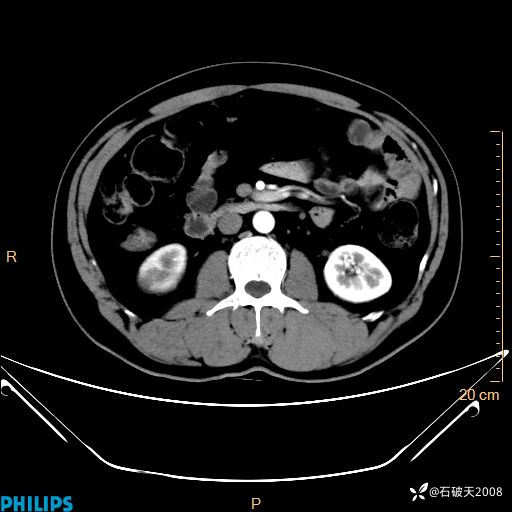

增强轴位